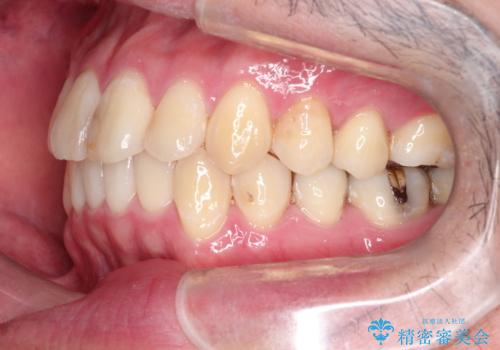

全体的ながたつきをインビザラインで改善

- 全体的ながたつきを主訴に来院されました。

歯と歯の間をわずかに削って、スペースをつくり並べる計画としました。

しっかりと、マウスピースの装着時間を守っていただいたので、スムーズに治療をおえることができました。